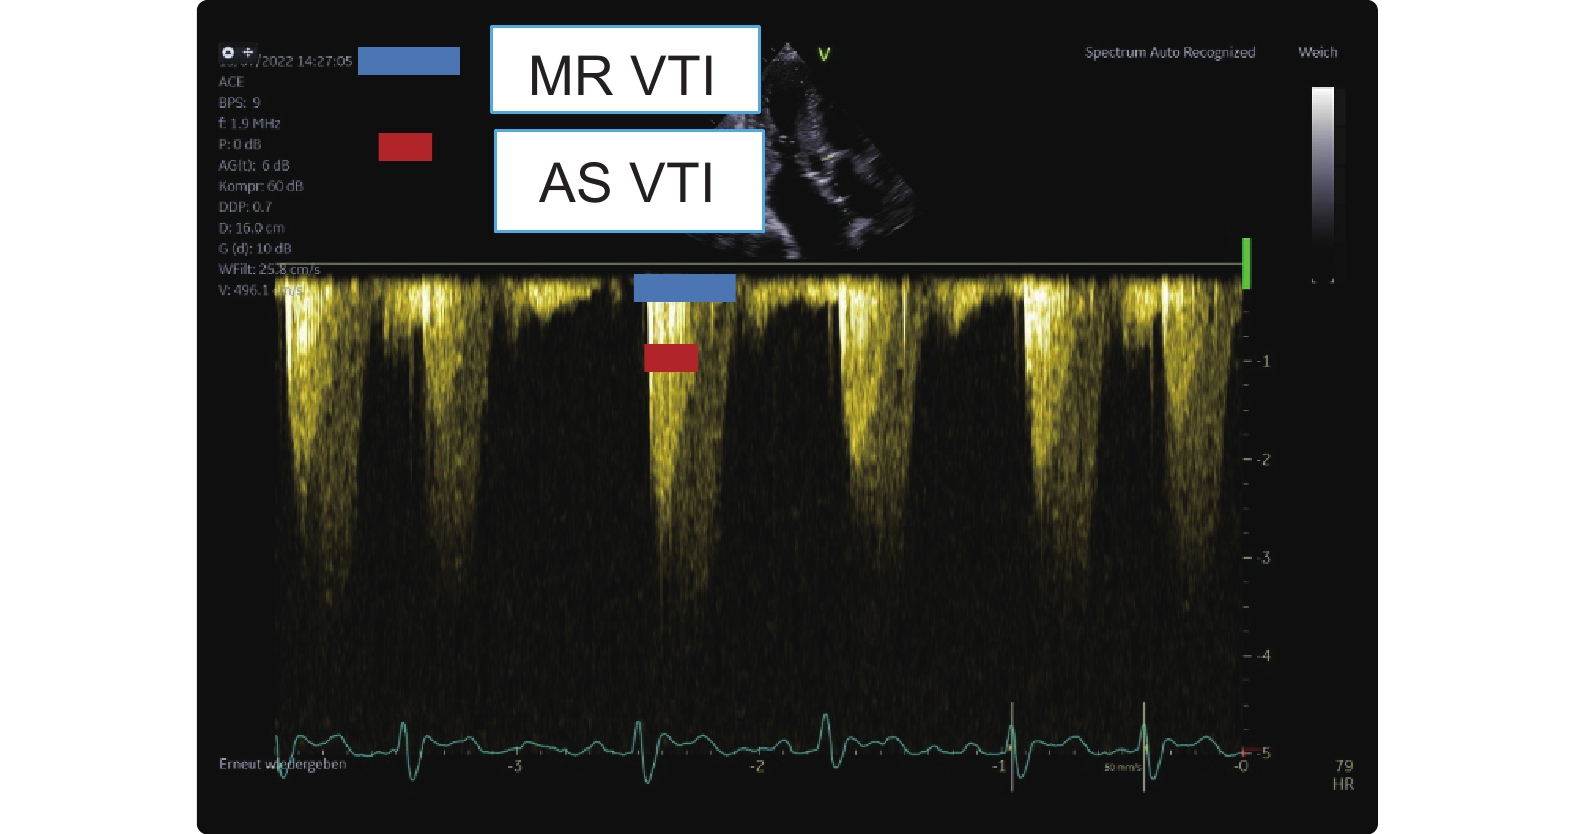

Zoghbi WA, Galan A, Quinones MA. Accurate assessment of aortic stenosis severity by Doppler echocardiography independent of aortic jet velocity. Am Heart J 1988; 116: 855-863.

Hagendorff A, Knebel F, Helfen A, Knierim J, Sinning C, Stöbe S, et al. Expert consensus document on the assessment of the severity of aortic valve stenosis by echocardiography to provide diagnostic conclusiveness by standardized verifiable documentation. Clin Res Cardiol 2020; 109: 271-288.

Gill H, Fernandes J, Chehab O, Prendergast B, Redwood S, Chiribiri A, et al. Evaluation of aortic stenosis: from Bernoulli and Doppler to Navier-Stokes. Trends Cardiovasc Med 2023; 33: 32-43.

Guzzetti E, Capoulade R, Tastet L, Garcia J, Le Ven F, Arsenault M, et al. Estimation of stroke volume and aortic valve area in patients with aortic stenosis: a comparison of echocardiography versus cardiovascular magnetic resonance. J Am Soc Echocardiogr 2020; 33: 953-963.e5.

Saikrishnan N, Kumar G, Sawaya FJ, Lerakis S, Yoganathan AP. Accurate assessment of aortic stenosis: a review of diagnostic modalities and hemodynamics. Circulation 2014; 129: 244-253.